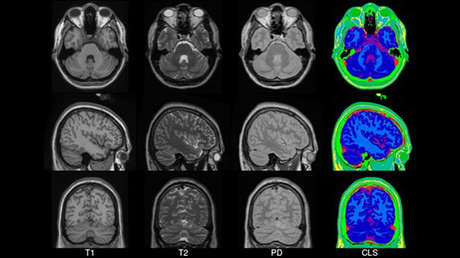

Con los datos recabados, el equipo midió el tamaño exterior y la microarquitectura de cada cerebro, con el objetivo de componer un "atlas cerebral" (IBA100) similar a aquellos que ya existen para la población caucásica europea y canadiense, o para chinos y coreanos.

El artículo, que ha aparecido publicado este mes en la revista Neurology India, considera imprescindibles este tipo de atlas para lograr una "normalización espacial", ya que se trata de un "paso crítico" en las técnicas automatizadas de análisis para procesar las imágenes obtenidas por resonancia magnética (IRM) y poder diagnosticar patologías.

Una vez unificados los datos, los autores del estudio pasaron a compararlos con análogos de los años 90 y otros más recientes del Instituto Neurológico de Montreal (Canadá), que se usan ampliamente como sistemas de referencia. Este análisis les permitió llegar a la conclusión inequívoca de que "hay una diferencia significativa entre el tamaño general del cerebro indio y el caucásico". El primero es normalmente menor en las tres dimensiones (largo, ancho, alto) que el otro y la diferencia "se extiende al nivel estructural".